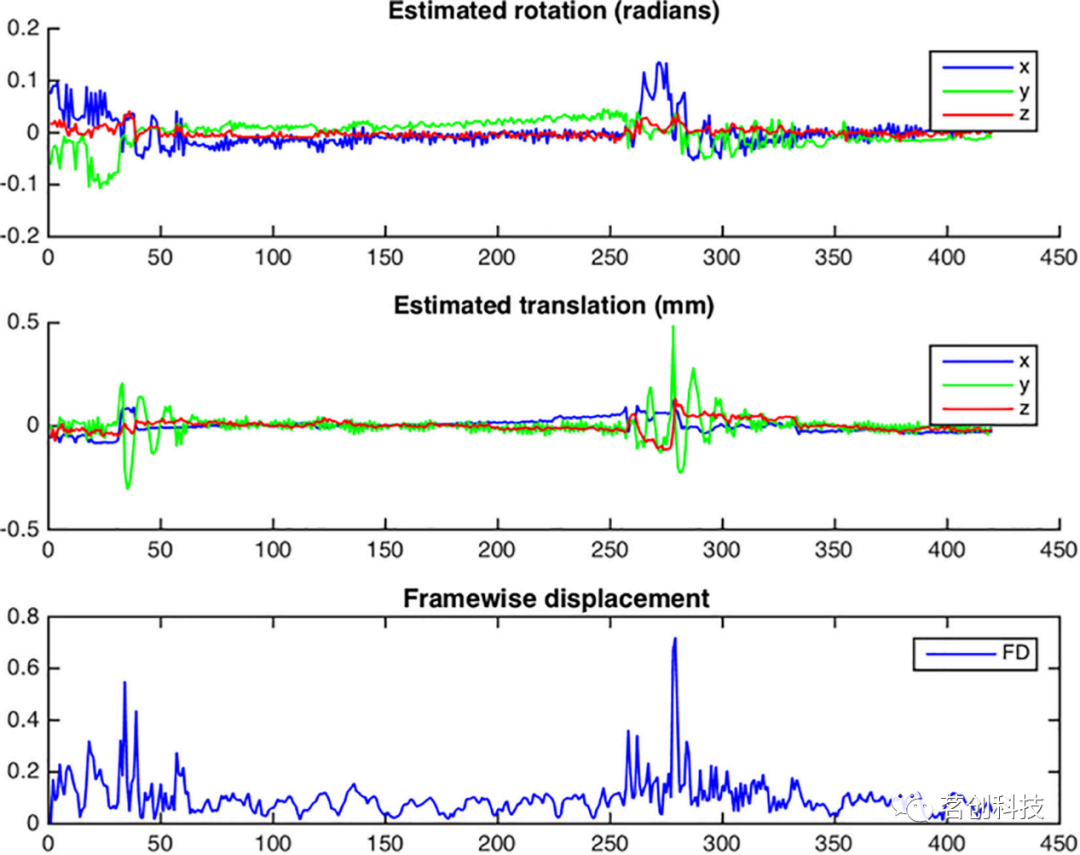

为了校正头动,需要基于6个运动参数(三个旋转参数和三个平移参数)获得运动估计。这是通过相对于参考的不同体积之间的刚体配准来完成的,在NeoRS中,参考是来自rsfMRI的第一个volume,用户也可以根据自己的需要进行更改。该NeoRS函数是使用FSL mcflirt执行的,其工作原理与成人相同,但是这里将平滑设置为0,因为平滑会在流程后期进行,并使用sinc插值。交叉重新配准的参数可以在Matlab函数cross_realign2.m中自定义。出于质量控制的目的,NeoRS创建了一个.png文件,其中可以评估每个volume的总旋转、平移和逐帧位移(FD)。逐帧位移的计算方法如Power等人(2012)所述。考虑到头部大小的差异,这里将使用半径为35mm而不是50mm的球体来进行计算,这大约对应于新生儿大脑皮层到头部中心的平均距离。运动校正后,将运动参数保存在一个文本文件中,进一步用于去噪。

在交叉配准之后,NeoRS将提供一个输出图,其中包含用于rsfMRI的每个volume交叉配准的旋转和平移信息,以及计算得到的逐帧位移(图9)。

图9.来自单个被试的头动示意图。